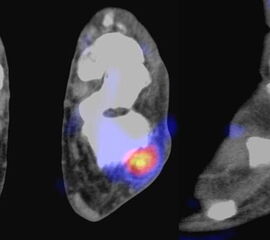

Nachfolgend 3 Fälle mit szintigraphisch nachweisbaren Tendinitiden in den Abbildungen 8.8., 8.9. und 8.10. Vergleichbare Fälle sind publiziert worden 697071.

Abbildung 8.8.a bis d: Patientin mit bekanntem Knick-Senk-Fuß. Anamnestisch Schmerzen in beiden Füßen, links > rechts seit ca. 2 Jahren. Fragestellung: Status der bekannten Fußwurzelarthrosen vor geplanter OP. Neben, unter anderem fortgeschrittenen Arthrosen im Naviculo-Cuneiforme-Gelenk, Nachweis einer Tibialis posterior-Sehnen-Tendinitis mit begleitender Periostitis/Ostitis am Malleolus postero-medial. Abbildung 8.8.a und b: in der Frühphase (2 Minuten nach Tracerinjektion) sind lineare Anreicherung des Tracers im Verlauf der linken Tibialis posterior Sehne zu sehen.  In der  Mineralisationsphase im SPECT/CT begleitende Periostitis/Ostitis am Malleolus postero-medial. Abbildung 8.8.c und d: Der Blick auf das CT im Weichteilfenster offenbart diffuse entzündliche Verdickungen im Verlauf der linken Tibialis posterior Sehne. Rechts unauffälliger Befund. Unten beispielhaft die schmerzhafte NC-Arthrose.

Abbildung 8.9. a bis c: Extern MRT-morphologisch V. a. Coalitio calcaneo-naviculare. Anamnestisch Schmerzen im linken OSG seit ca. 1,5 Jahren, gehäuftes „Umknicken“ des linken Fußes, Pes planus bds.. Abbildung 8.9.a zeigt die 3D-Früh-SPECT aus verschiedenen Blickwinkeln. Wie in Abbildung 8.8.a findet sich hier eine deutliche lineare Tracerakkumulation im Verlauf der linken Tibialis posterior Sehne. Abbildung 8.9.b: In der Mineralisationsphase wie auch im vorhergehenden Fall ossäre Reaktion postero-medial am Mallelolus medialis als Zeichen einer chronischen Tendinitis. Die Durchsicht der 7 Wochen zuvor angefertigten externen MRT bestätigte den Befund (er war leider nicht beschrieben worden). Im SPECT/CT wurde eine Coalitio ausgeschlossen.

Abbildung 8.10.a bis e: Patient mit Verdacht auf symptomatisches Os peronaeum. In der Früh-SPECT/CT eindeutiger Nachweis einer ausgeprägten Tendinitis der Peronealsehnen links. In der Mineralisationsphase Stessreaktion im Bereich eines mehrgeteilten Os peroneaum links und lateral Calcaneus.